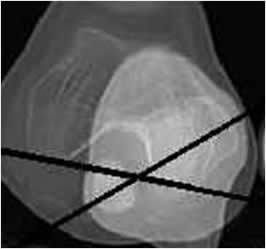

Distancia tuberosidad tibial/surco femoral (TA/GT: Tuberosidad anterior/Garganta troclear).

Medido mediante TAC, con rotación lateral de los pies de 15º. Se realizan cortes superpuestos sobre la mitad de la patela y que pase por los cóndilos femorales y otro en la tibia proximal, a nivel de la tuberosidad. (1, 3). El estudio se realiza en reposo y con contracción de los cuádriceps y flexión de 15º en las rodillas, utilizando un soporte. (22). (Fig 86).

Se traza una línea tangencial que pase por la parte posterior de los cóndilo femorales y de allí una perpendicular, que cruce por la parte mas profunda o el centro del surco troclear. (Línea del surco). La otra es una paralela a la línea del surco y que pasa por la parte mas alta de la tuberosidad tibial. (Línea de la tuberosidad tibial). (1, 3, 18).

Se mide la distancia entre la línea del surco y la de la tuberosidad de la tibia, que tiene un rango entre 7 y 17 mm y un promedio de 15 mm. (3, 18). Aumenta en la luxación recidivante de la rotula, inestabilidad patelar y artrosis patelofemoral, siendo mayor de 20 mm. (3). (Fig 84 y 85).

Fig 84. TA-GT.

A: TAC axial. Línea perpendicular a la bicondilea posterior y que pasa por la parte mas profunda de la garganta troclear.

B: TAC axial. Línea paralela a la del surco, que cruza por la parte mas alta de la tuberosidad tibial.

Se superponen y se mide la distancia entre la linea del surco y la linea de la tuberosidad tibial.

Fig 85. TA-GT.

Medición del ángulo con el software de la máquina, con una distancia de 15 mm.